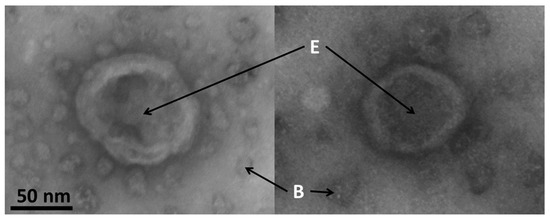

3.7. Electron Microscopy of Exosomes

Typical images of exosomes made by electron microscopy are shown in the Figure 7. The size of the exosomes in this study was confirmed to be around 85 nm.

Exosomes appeared to have a spherical shape with a typical central inflation caused by samples preparation and drying. These morphological data clearly demonstrate the exosomal identity of samples isolated using a combination of flow cytometry and magnetic beads.

Figure 7. Typical images of exosomes made by electron microscopy. E: exosomes; B: magnetic beads. Detailed information on the preparation of the samples is found in Section 2.8. Scale bar = 50 nm.